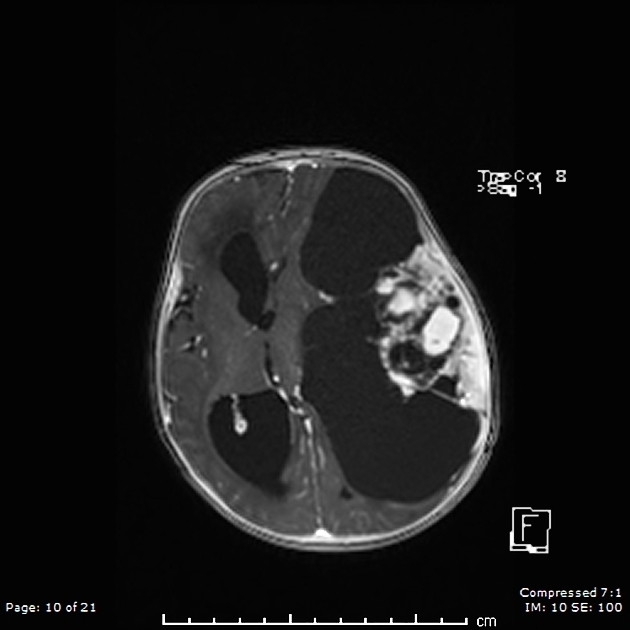

Imaging features of ganglioglioma

1. Most common neoplastic cause of temporal lobe seizures in adolescents/young adults.

2. Although its imaging appearance varies, the

most common presentation is a superficial mixed cystic and solid mass; the solid components often present as a mural nodule and are hyperintense on T2 sequences.

As the lesion is cortically based, cortical expansion and overlying bony remodeling is often seen.

CALCIFICATIONS and enhancement of

solid components are noted in approximately half of cases.

Meningeal enhancement and surrounding edema is mild,

when present.